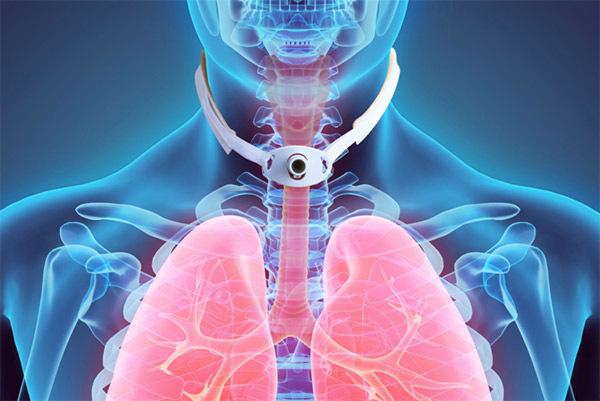

Saiba maisTraqueostomia

A traqueostomia é a abertura realizada na parede anterior da traqueia comunicando-a com o meio externo com a finalidade de facilitar a respiração, nesta abertura é introduzida uma cânula específica que pode ser conectada a aparelhos que auxiliam a respiração.

Colocação de Órtese Traqueal

As órteses ou próteses traqueais são colocadas no interior da traqueia nos casos de estenose traqueal, visando tratar uma obstrução seja ela causada por colabamento da traqueia, tumores, inflamação ou outra lesões.

Traqueoplastia, o que é, cuidados e pós

A traqueoplastia é a cirurgia definitiva para tratamento da estenose traqueal. Sua maior vantagem é…